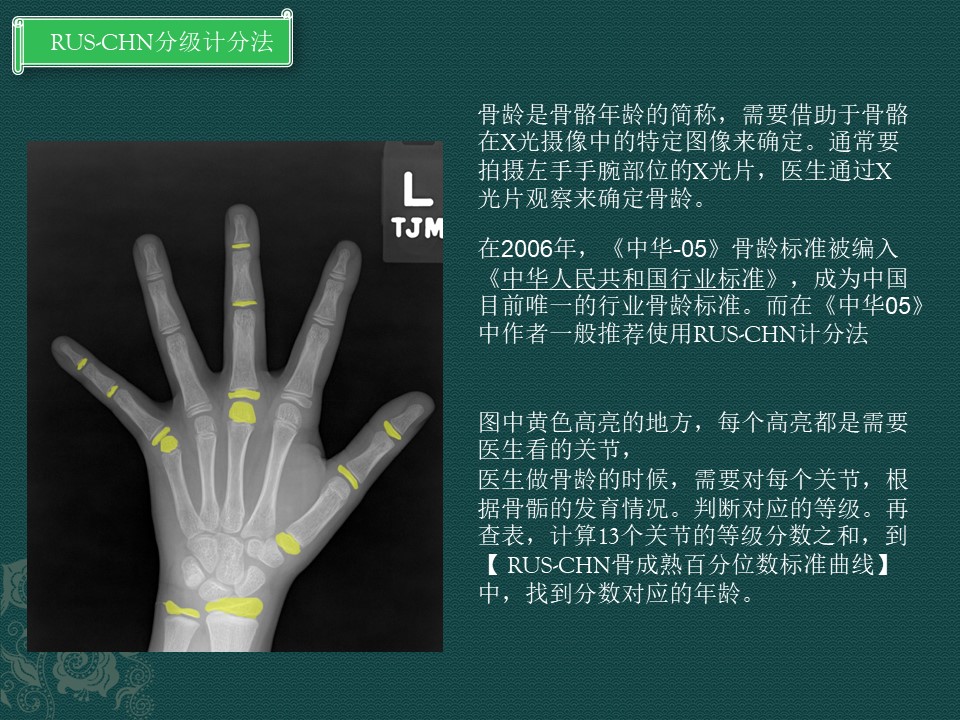

骨龄是骨骼年龄的简称,需要借助于骨骼在X光摄像中的特定图像来确定。通常要拍摄左手手腕部位的X光片,医生通过X光片观察来确定骨龄。

骨龄和RUS-CHN计分法

这个放射临床骨龄工作,可以看出是一项耗精力耗时间的工作。

需要对照13个关节的图谱才能计算骨龄